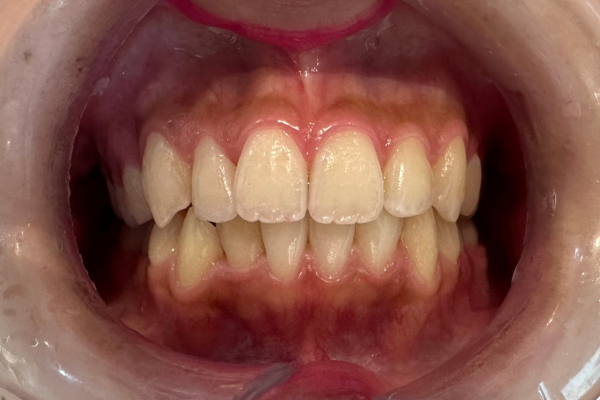

叢生|マウスピース矯正(インビザライン)の症例

インビザライン

上下の前歯のガタツキ

1年半

装着中の違和感

虫歯、歯肉炎